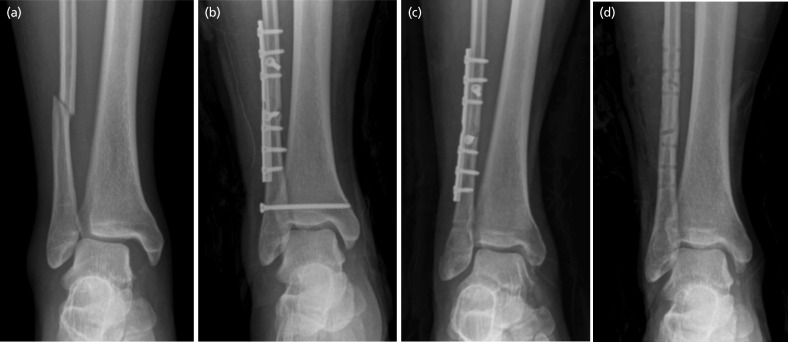

Materials and methods: Thirty patients were treated with dynamic fixation (DF group) and 28 patients with static screw fixation (SF group). The primary outcome was Olerud-Molander Ankle Outcome Score. The secondary outcome were Visual Analogue Scale score and American Orthopedic Foot and Ankle Society score, radiographic outcomes, complications and cost effectiveness. To evaluate the radiographic outcome, the tibiofibular clear space, tibiofibular overlap, and medial clear space were compared using the pre-operative and last follow-up plain radiographs. To evaluate the cost effectiveness, the total hospital cost was compared between the two groups.

Results: There was no significant difference in primary outcome. Moreover, there were no significant difference in secondary outcome including Visual Analogue Scale score and American Orthopedic Foot and Ankle Society score and radiographic outcome. Two cases of reduction loss and four cases of screw breakage were observed in the SF group. No complication in the DF group was observed. Dynamic fixation was more cost effective than static screw fixation with respect to the total hospital cost.